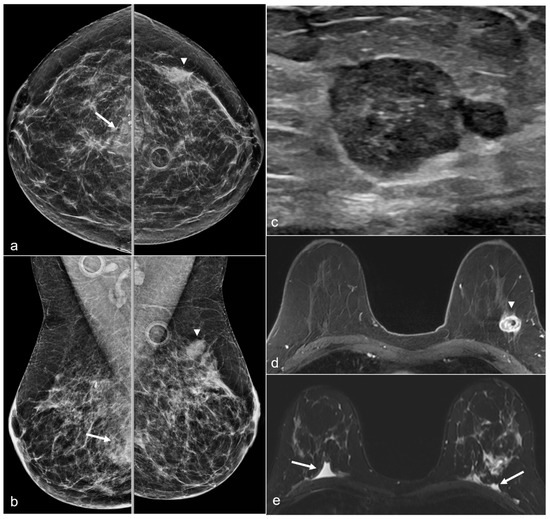

Figure 16. A 52-year-old woman with a history of subglandular silicone implants. Prior mammograms with implant displaced views were negative. A screening mammogram with bilateral CC and MLO views one year after BES (a) demonstrates a spiculated mass in the left lower inner quadrant (arrow), which was biopsied under ultrasound guidance with pathology revealing invasive ductal carcinoma. T1-weighted post-contrast MRI axial images demonstrate areas of fat necrosis in both breasts ((b,c), arrowheads). An enhancing mass with a biopsy clip is seen adjacent to the surgical scar ((c), arrow) in the left breast representing the biopsy proven carcinoma.